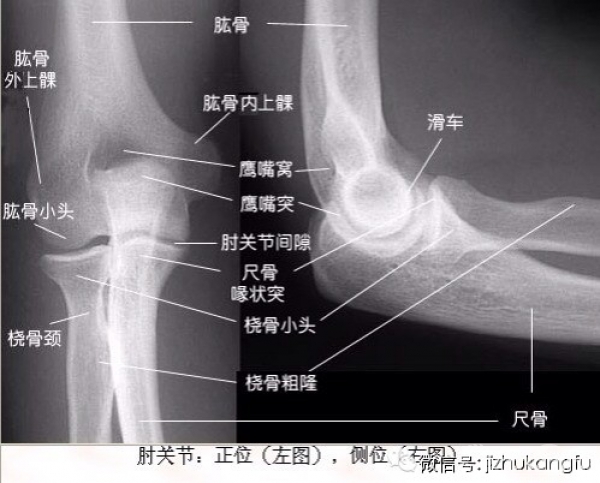

1四肢关节